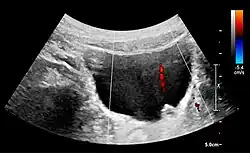

Figure 21. Left hydroureter with ureteric jet. No stone is visible. The red color in the color box represents motion towards the transducer as defined by the color bar.[1]